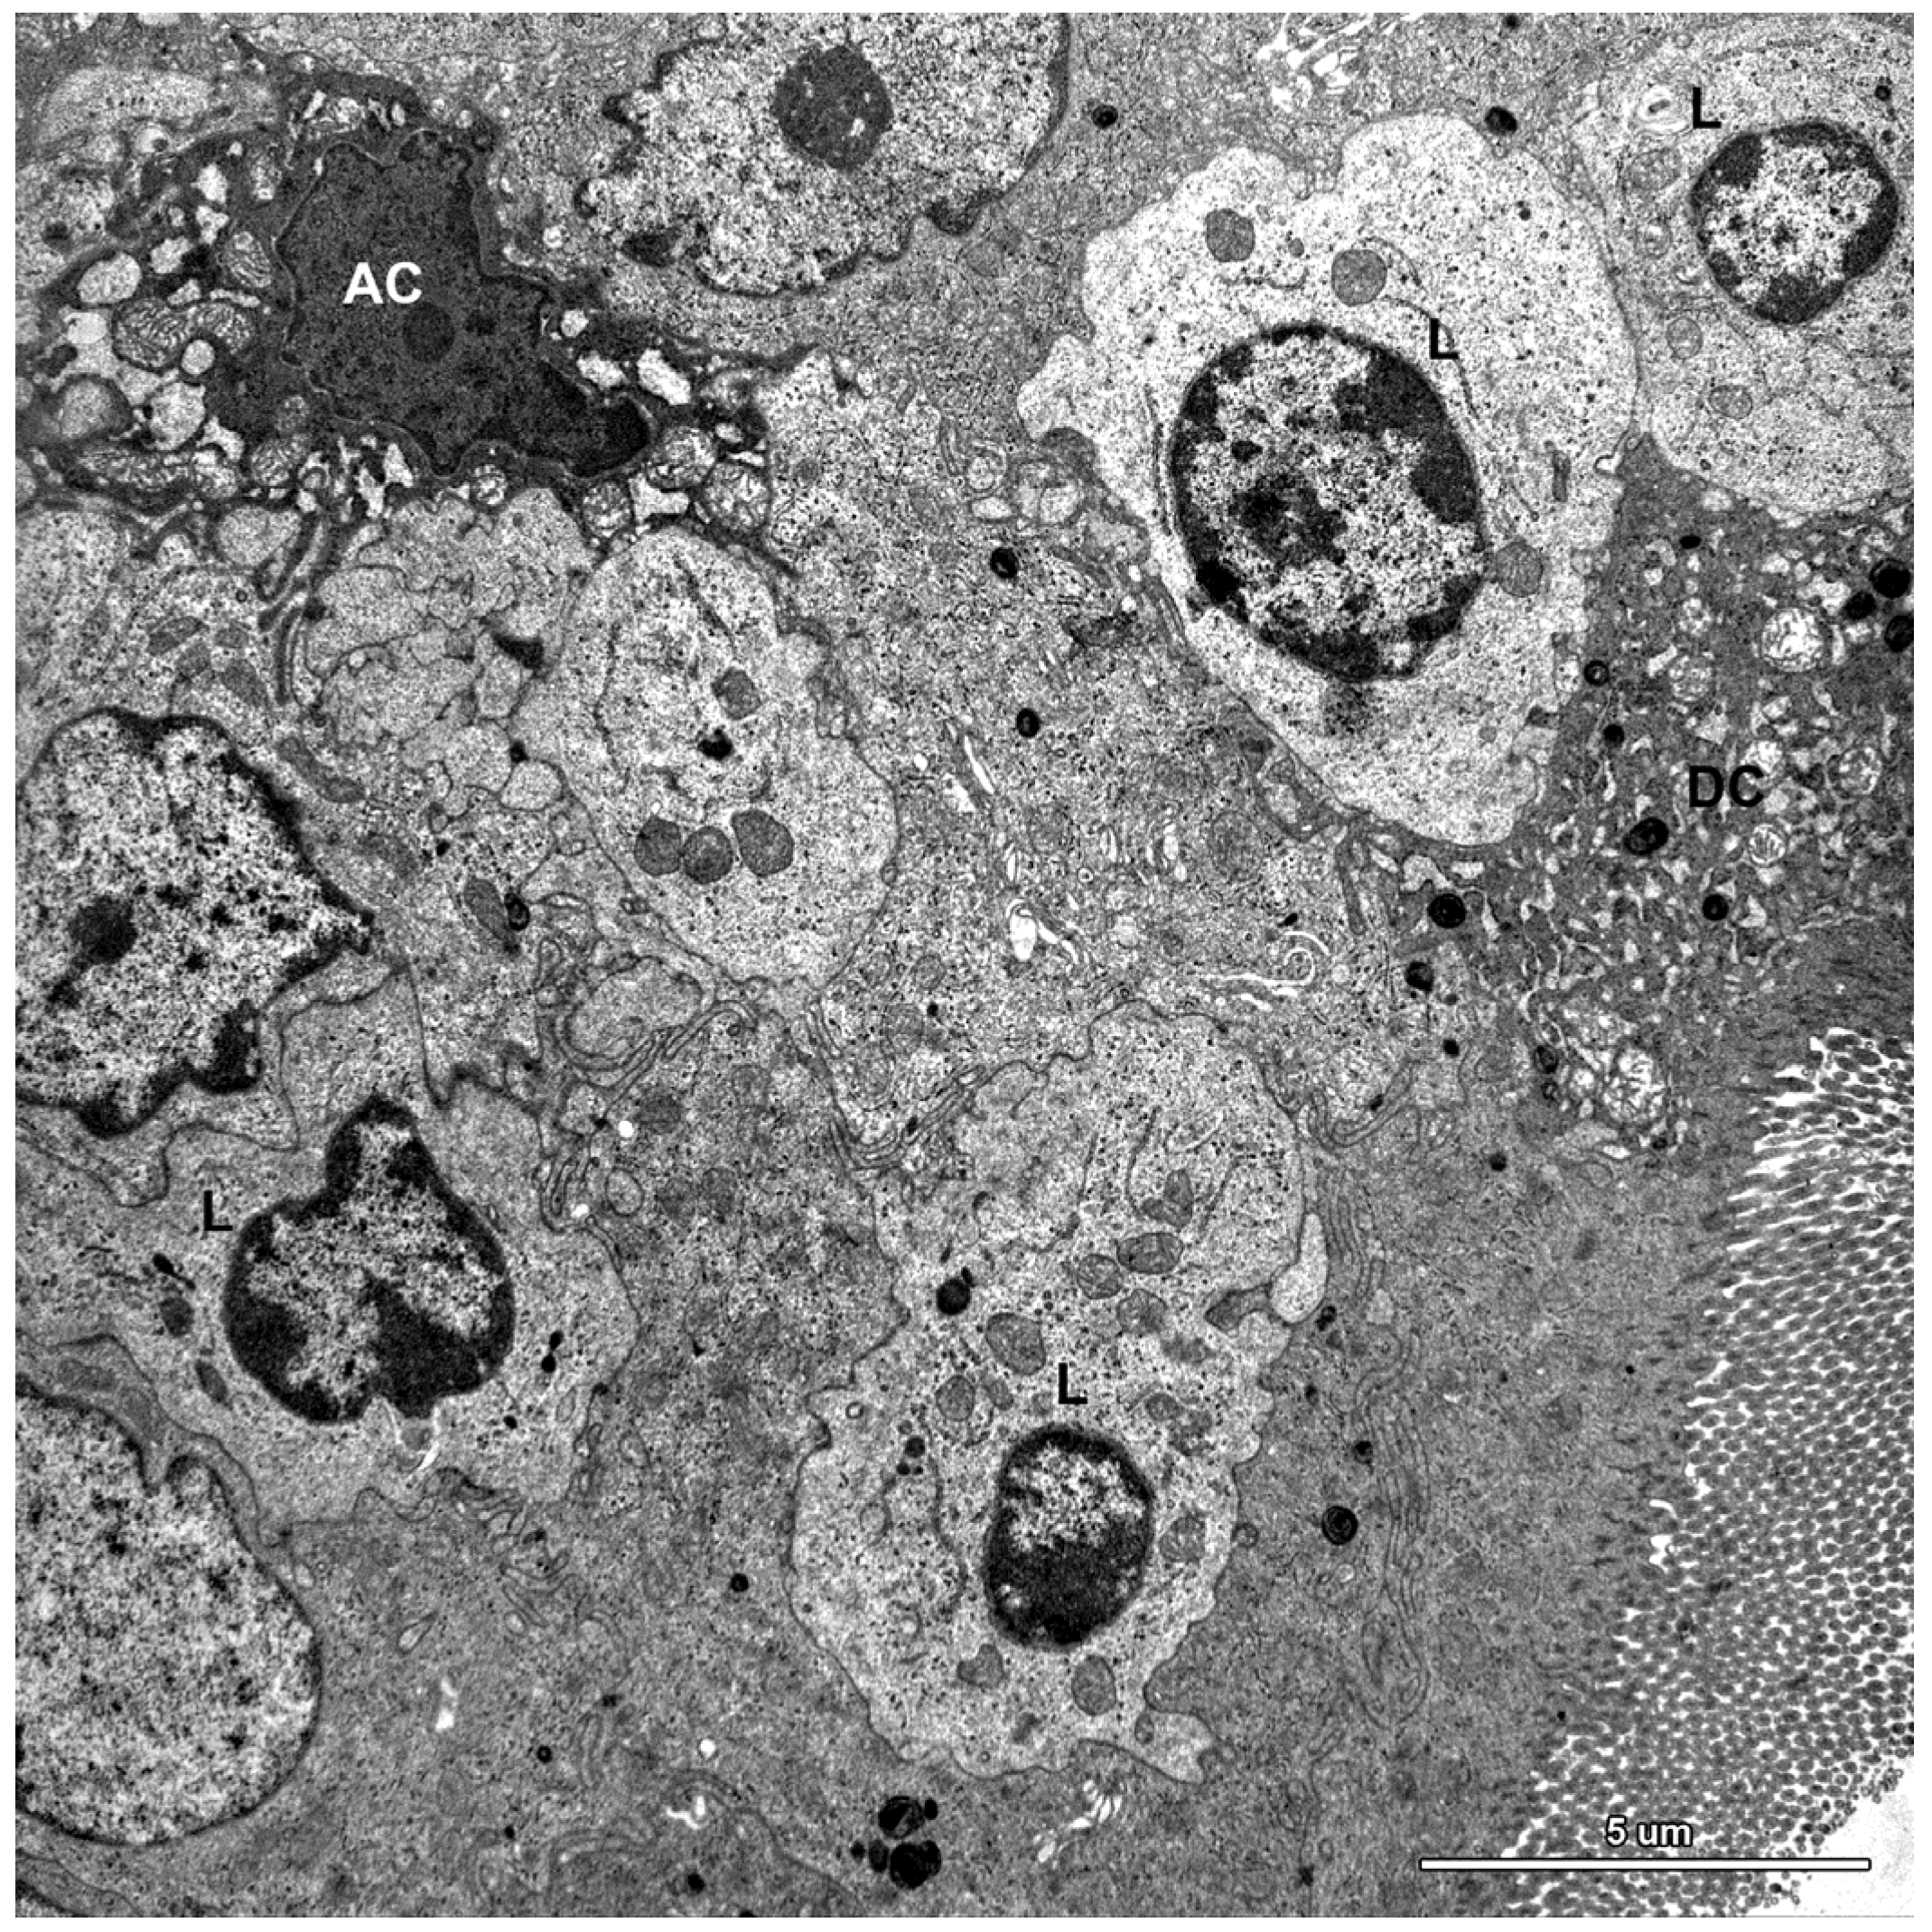

Figure 9.

Ultrastructure of the jejunal mucosa epithelium in a pig that received DON for six weeks. Note numerous lymphocytes (L) between epithelial cells, degenerating adsorptive enterocytes (DC), and apoptotic cells (AC).

A characteristic feature of the epithelium covering the villi was the presence of numerous lymphocytes in samples taken from pigs that received ZEN for one week as well as ZEN, DON or DON + ZEN for three and six weeks (Figure 7, Figure 8 and Figure 9).

Some degenerating cells and apoptotic cells were found in the epithelium in all animals (Figure 9); however, there were no difference in the frequency of their occurrence between groups.